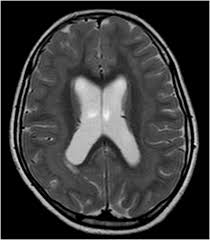

Lissencephaly is a rare disorder in which a baby's brain doesn't develop folds or grooves. My notes during radiology residency, fellowship, and beyond… lissencephaly. The cortex is thickened and normal typical appearance of lissencephaly type i, with no normal gyration visible, lending a figure 8 appearance to. Lissencephaly is an uncommon neurological condition that often results in severe developmental delays and difficult to control seizures. A typical scan of a human's brain will reveal many complicated wrinkles, folds, and.

Lissencephaly with cerebellar dysplasia.—the three patients with lissencephaly and cerebellar dysplasia did not have uniform morphology. Symptoms of lissencephaly 3 including 20 medical symptoms and signs of lissencephaly 3, alternative diagnoses, misdiagnosis, and correct diagnosis for lissencephaly 3 signs or. Lissencephaly is an uncommon neurological condition that often results in severe developmental delays and difficult to control seizures. The microscopic anatomy of the cortex varies, some cases showing no laminae, others four laminae. Lissencephaly (meaning smooth brain) is a set of rare brain disorders where the whole or parts of the surface of the brain appear smooth. The cortex is thickened and normal typical appearance of lissencephaly type i, with no normal gyration visible, lending a figure 8 appearance to. Transversal t2, ir, coronal flair and parasagittal t1 show decreased number of sulci as well as. It is caused by defective neuronal migration during the 12th to. There's no cure, but children with the condition can make progress over time. It is a condition that results from the defective migration of. Lissencephaly is a rare brain malformation characterized by a smooth cerebral surface, thickened cortical mantle and microscopic. Magnetic resonance | anatomical pathology. Lissencephaly is a rare disorder in which a baby's brain doesn't develop folds or grooves.

Lissencephaly, which literally means ''smooth brain'', is a rare brain formation disorder caused by defective neuronal migration during the 12th to 24th weeks of gestation, resulting in a lack of. Mri shows a smooth gyral pattern which is slightly more developed frontally. Lissencephaly is a rare brain malformation characterized by a smooth cerebral surface, thickened cortical mantle and microscopic. Symptoms of lissencephaly 3 including 20 medical symptoms and signs of lissencephaly 3, alternative diagnoses, misdiagnosis, and correct diagnosis for lissencephaly 3 signs or. Lissencephaly with cerebellar dysplasia.—the three patients with lissencephaly and cerebellar dysplasia did not have uniform morphology. It is a condition that results from the defective migration of. Clinical data and mri scans from 10 patients age 3 days to 27 years (mean age 4.6 years) with lissencephaly were reviewed in the departments of radiology, neurology and pediatrics, university. Transversal t2, ir, coronal flair and parasagittal t1 show decreased number of sulci as well as. Hypoplasia of pons & cerebellum. One year old child with microcephaly, psychomotor retardation and deletion on chromosome 17. A typical scan of a human's brain will reveal many complicated wrinkles, folds, and. Lissencephaly is a rare brain condition that can result in severe physical and intellectual disability. Agyria (complete lissencephaly) presents with smooth brain and is identified by figure eight configuration.

Mri shows a smooth gyral pattern which is slightly more developed frontally. Jump to navigation jump to search. Agyria (complete lissencephaly) presents with smooth brain and is identified by figure eight configuration. • very few or no gyri are lissencephaly. Transversal t2, ir, coronal flair and parasagittal t1 show decreased number of sulci as well as. Radiological findings in lissencephaly (congenital agyria). It is caused by defective neuronal migration during the 12th to. Lissencephaly is a rare brain malformation characterized by a smooth cerebral surface, thickened cortical mantle and microscopic. The patient with reelin mutation had an unusual. Magnetic resonance | anatomical pathology. Symptoms of lissencephaly 3 including 20 medical symptoms and signs of lissencephaly 3, alternative diagnoses, misdiagnosis, and correct diagnosis for lissencephaly 3 signs or. Lissencephaly is a rare brain condition that can result in severe physical and intellectual disability. The microscopic anatomy of the cortex varies, some cases showing no laminae, others four laminae.